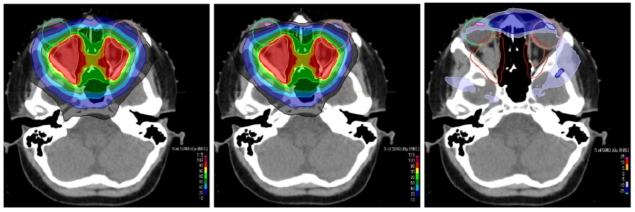

用于視神經(jīng)膠質(zhì)瘤質(zhì)子治療的(左)非準直計劃和(中)具有孔徑的計劃的劑量分布;右側(cè)面板顯示了劑量差異。光圈的使用減少了眼睛晶狀體的劑量(藍色和洋紅色輪廓)。(提供者:CC BY 4.0 /前ONCOL。

PBS 質(zhì)子治療中使用的筆形光束通常具有 1 厘米(半高全寬)或更大的光斑尺寸,這會阻礙靶體積附近有風(fēng)險的器官的保留。橫向的劑量下降也限制了覆蓋目標同時將正常組織的劑量保持在可容忍水平的選擇。WPE 團隊證明,使用靜態(tài)孔徑來修剪這些點掃描場可以減少對眼部晶狀體和腦干等危險器官的劑量,并且在六個腦腫瘤病例中減少了對大腦和海馬體的劑量。

該研究包括六例腦腫瘤顱咽管瘤,目標位于重要的危險器官附近,包括腦干、視神經(jīng)、交叉和海馬。對丘腦、腦干和海馬使用具有靜態(tài)孔徑的 PBS 的最大好處是,平均劑量分別降低了 5.5、5.6 和 3.1 Gy(RBE)。在兩種情況下,眼睛晶狀體的平均劑量降至 5 Gy(RBE) 以下,這是不使用光圈就無法實現(xiàn)的。